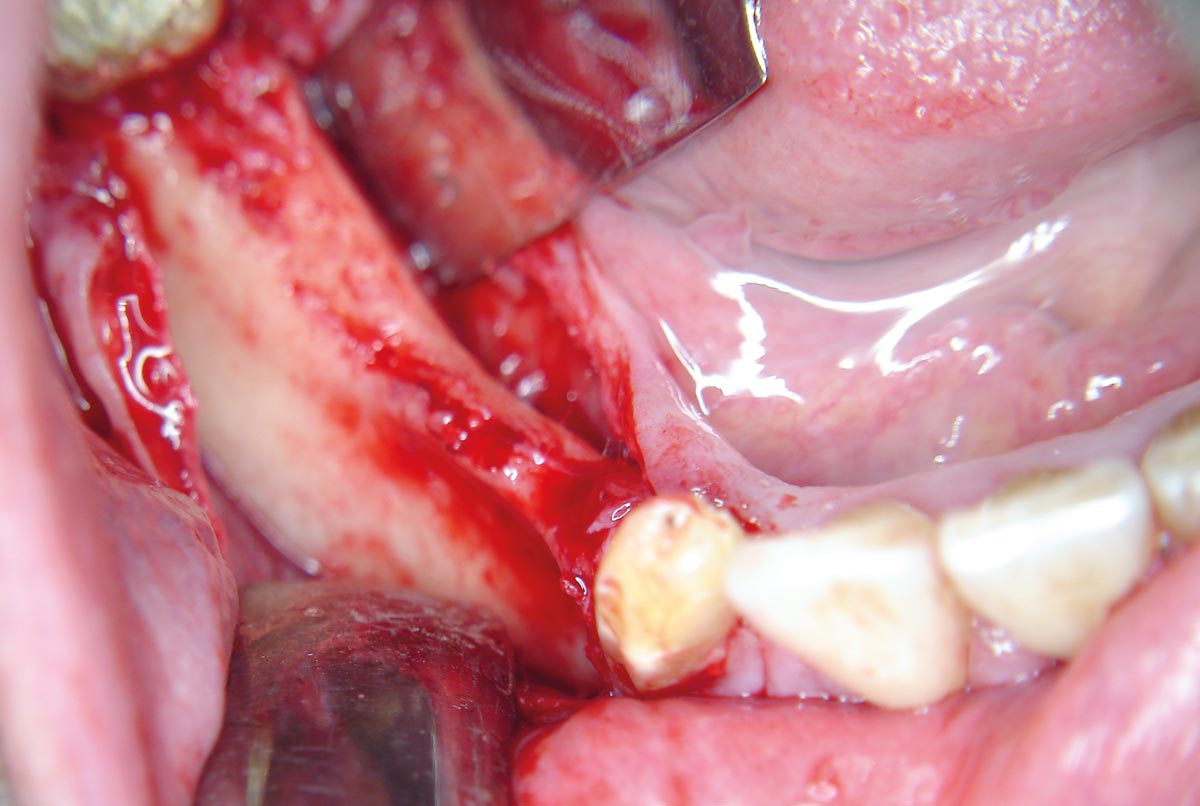

10 / 20 - Placing of pilot drills into the new formed bone tissueHorizontal ridge augmentation with maxgraft® cortico - M.Sc. E. Kapogianni

11 / 20 - Insertion of two dental implants in regio 44 and 46Horizontal ridge augmentation with maxgraft® cortico - M.Sc. E. Kapogianni